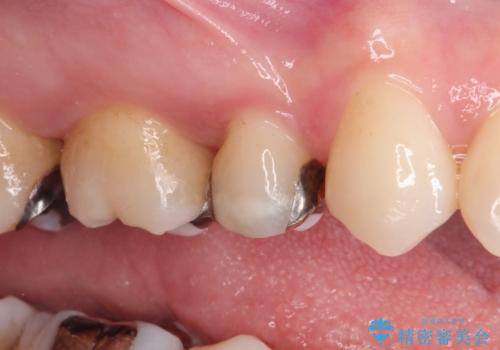

笑ったら銀歯が見える。 セラミックインレーによる治療

- 笑ったときに銀の詰め物が見えることを主訴に来院されました。

セラミックインレーにて修復を行いました。

保険治療で使える材料には制限があり、見た目だけでなく精度でも劣ります。当院でのセラミックインレーは歯とのつなぎ目を拡大鏡で確認して精度高く仕上げるため、むし歯のリスクを限りなく少なくできるよう治療します。